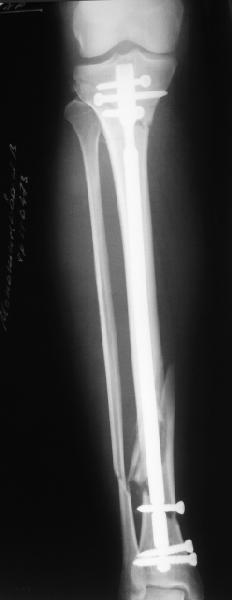

A typical case is attached, also an image with intra-op reduction obtained by a small wire distractor, in the moment of insertion a Poller wire in AP direction. Fixation by a SIGN nail. Despite the fibula was not fixed healing was obtained with the unchanged alignment.

Отправитель: Alexander Chelnokov 21 Май 2006, 23:21

I am just trying to illustrate that prevention of 1)tibial valgus and 2)loss of reduction can be provided without fibular plating. Small changes of conventional nailing techniques allow to maintain reduction of the tibia reliably without adjunctive fibular stabilization.

In delayed cases acute length restoration performed only in the tibia may leave the fibula shortened thus change the mortise. So it is reasonable to restore length of both bones simultaneously by distractor and fix the fibula not with open reduction and plating but just by a single perQ screw. Example attached.

На одной опоре, расположенной чуть дистальнее обычного, были закреплены 4 спицы, проведенные во фронтальной плоскости, по 2 в передней и задней части смежных фрагментов. Закреплены так, чтобы при их натяжении создалась компрессия. Картинка в приложении.